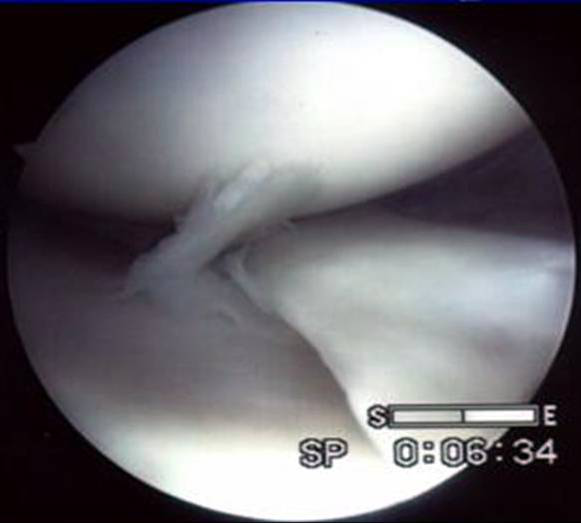

桶柄裂

探察桶柄裂

桶柄裂取出